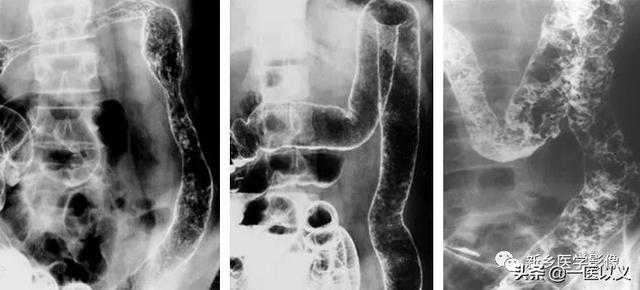

Alors que le lavement baryté joue un rôle important dans le diagnostic des patients atteints de colite ulcéreuse à un stade intermédiaire ou avancé.Un œdème et une ulcération de la muqueuse intestinale peuvent être détectés.

Critères diagnostiques de la colite ulcéreuse : ① exclure la dysenterie bacillaire, la colite amibienne, la schistosomiase, la tuberculose intestinale, la maladie de Crohn, l'entérite radique et d'autres causes d'inflammation du côlon ; ② avoir un tableau clinique typique et au moins une endoscopie ou une radiographie des changements caractéristiques de 1 ; ③ les symptômes cliniques ne sont pas typiques, mais il y a une coloscopie ou une radiographie typique ou une biopsie pathologique pour confirmer la colite ulcéreuse ; ③ les symptômes cliniques ne sont pas typiques, mais il y a une coloscopie ou une radiographie typique ou une biopsie pathologique pour confirmer la colite ulcéreuse.